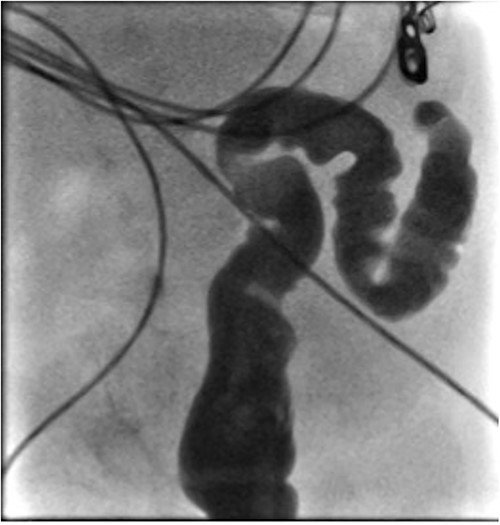

He presented at 6 weeks of age with circulatory shock requiring inotropic support and a short history of sudden abdominal distension and non bilious vomiting. He had been having regular episodes of SVT, all self limiting. Laparotomy demonstrated malrotation and a 540°midgut volvulus with extensive bowel necrosis. A fulcrum of ileum was densely adherent to the descending colon. Following intestinal resection he was left with 40 cm of small bowel from the duodenojejunal flexure, 2 cm of distal ileum and an intact colon. Following recovery from this acute episode he was managed for intestinal failure. A contrast enema was performed 10 days later in advance of stoma closure to examine the area of descending colon to which the ileum had been adherent at laparotomy. This demonstrated failure of passage of contrast proximal to the mid descending colon consistent with acquired colonic atresia (Fig. 1). Due to ongoing high stoma output and inability to progress enteral feeds, the infant proceeded to laparotomy, closure of jejunostomy, resection of colonic atresia, and anastomosis at 3 months of age. Macroscopic evidence of the atresia was encountered (Fig. 2). Histology reported a narrow calibre colon to either side of the atresia with fibrotic submucosa, focal fibrovascular proliferation, and clusters of giant cells. He subsequently achieved enteral autonomy.

Contrast enema showing failure of passage of contrast beyond descending colon.